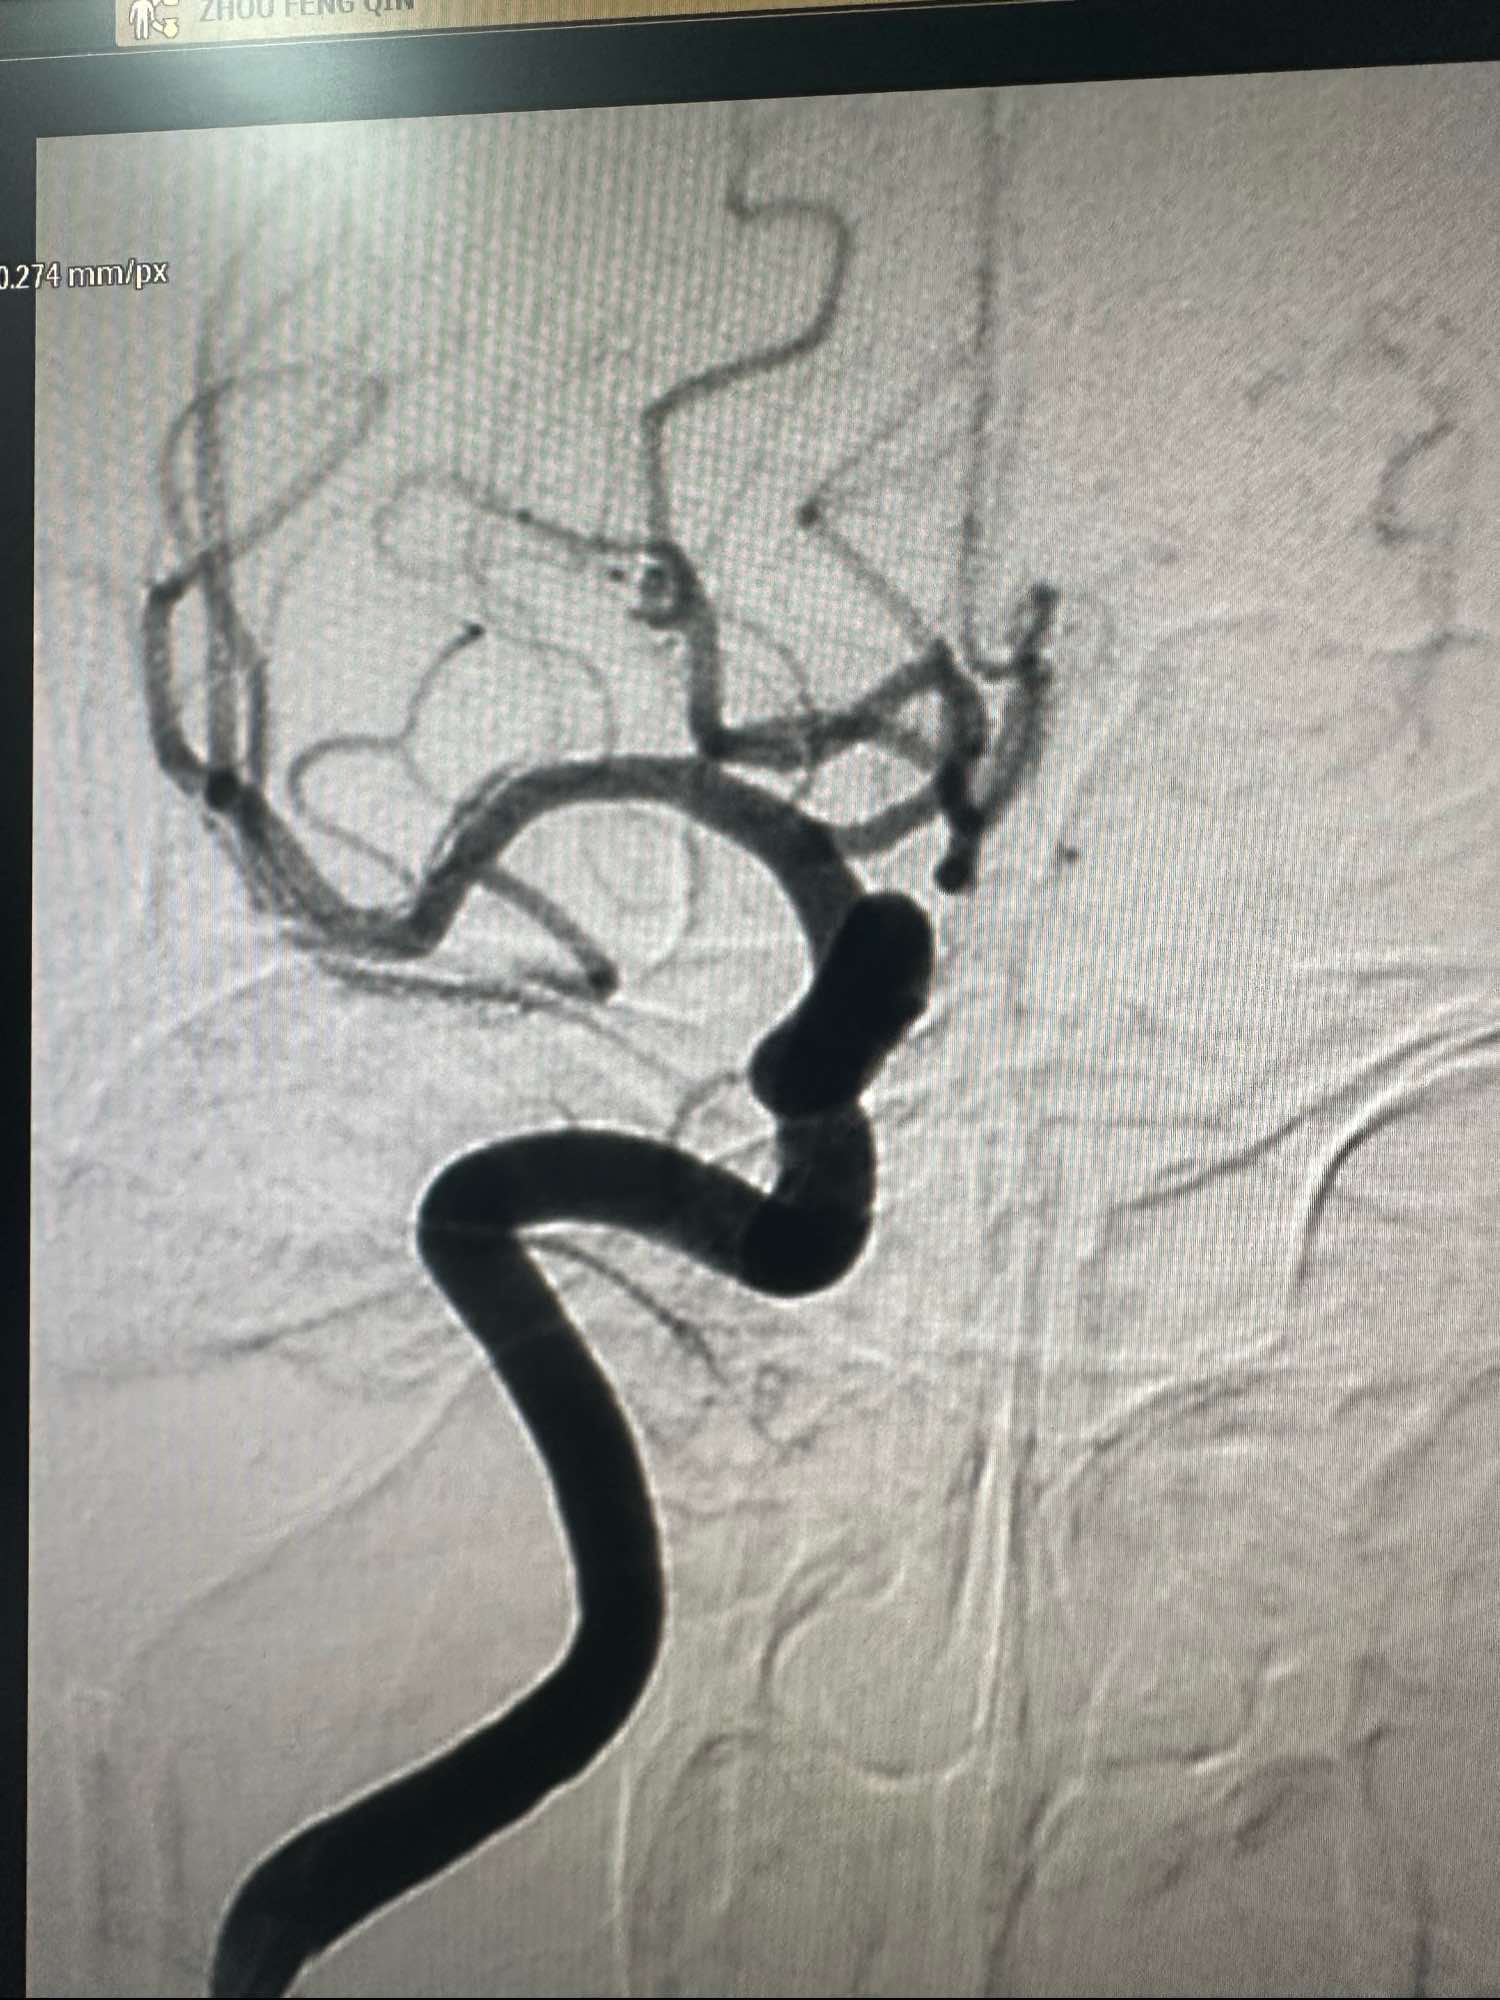

左侧颈内动脉造影3D